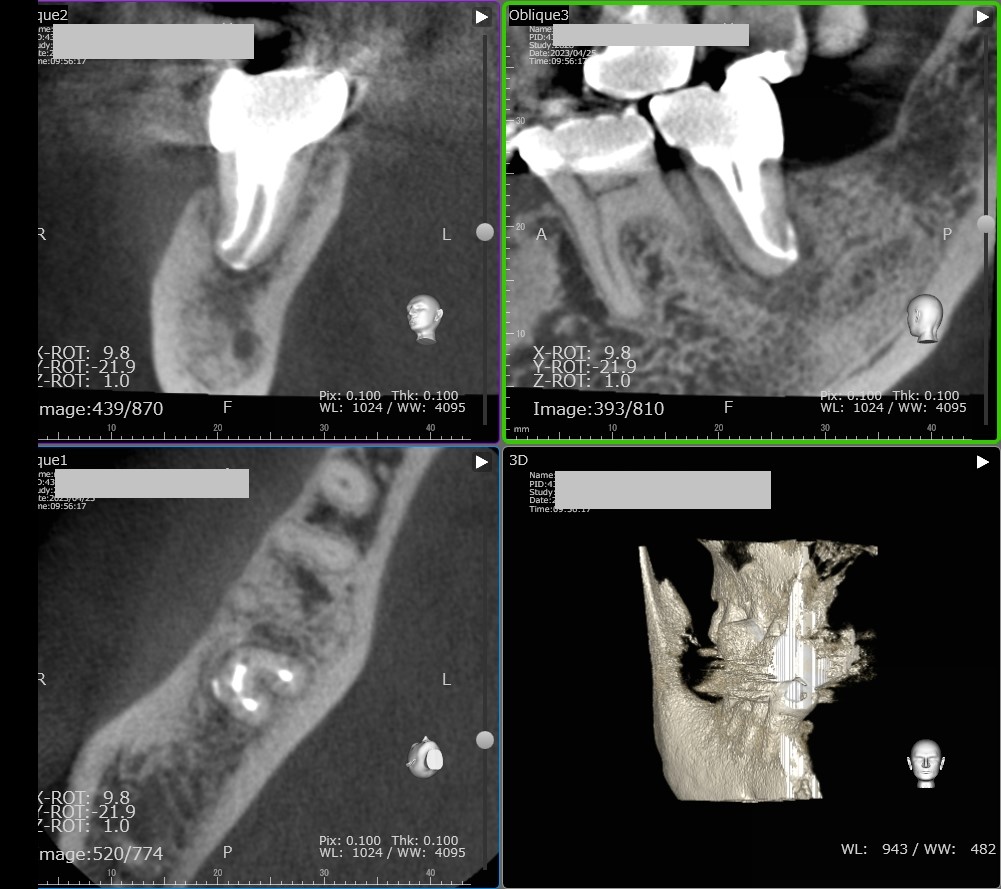

上顎奥歯の根管治療 ファイル破折除去

さて 今回は奥歯の根管治療の症例を紹介します。